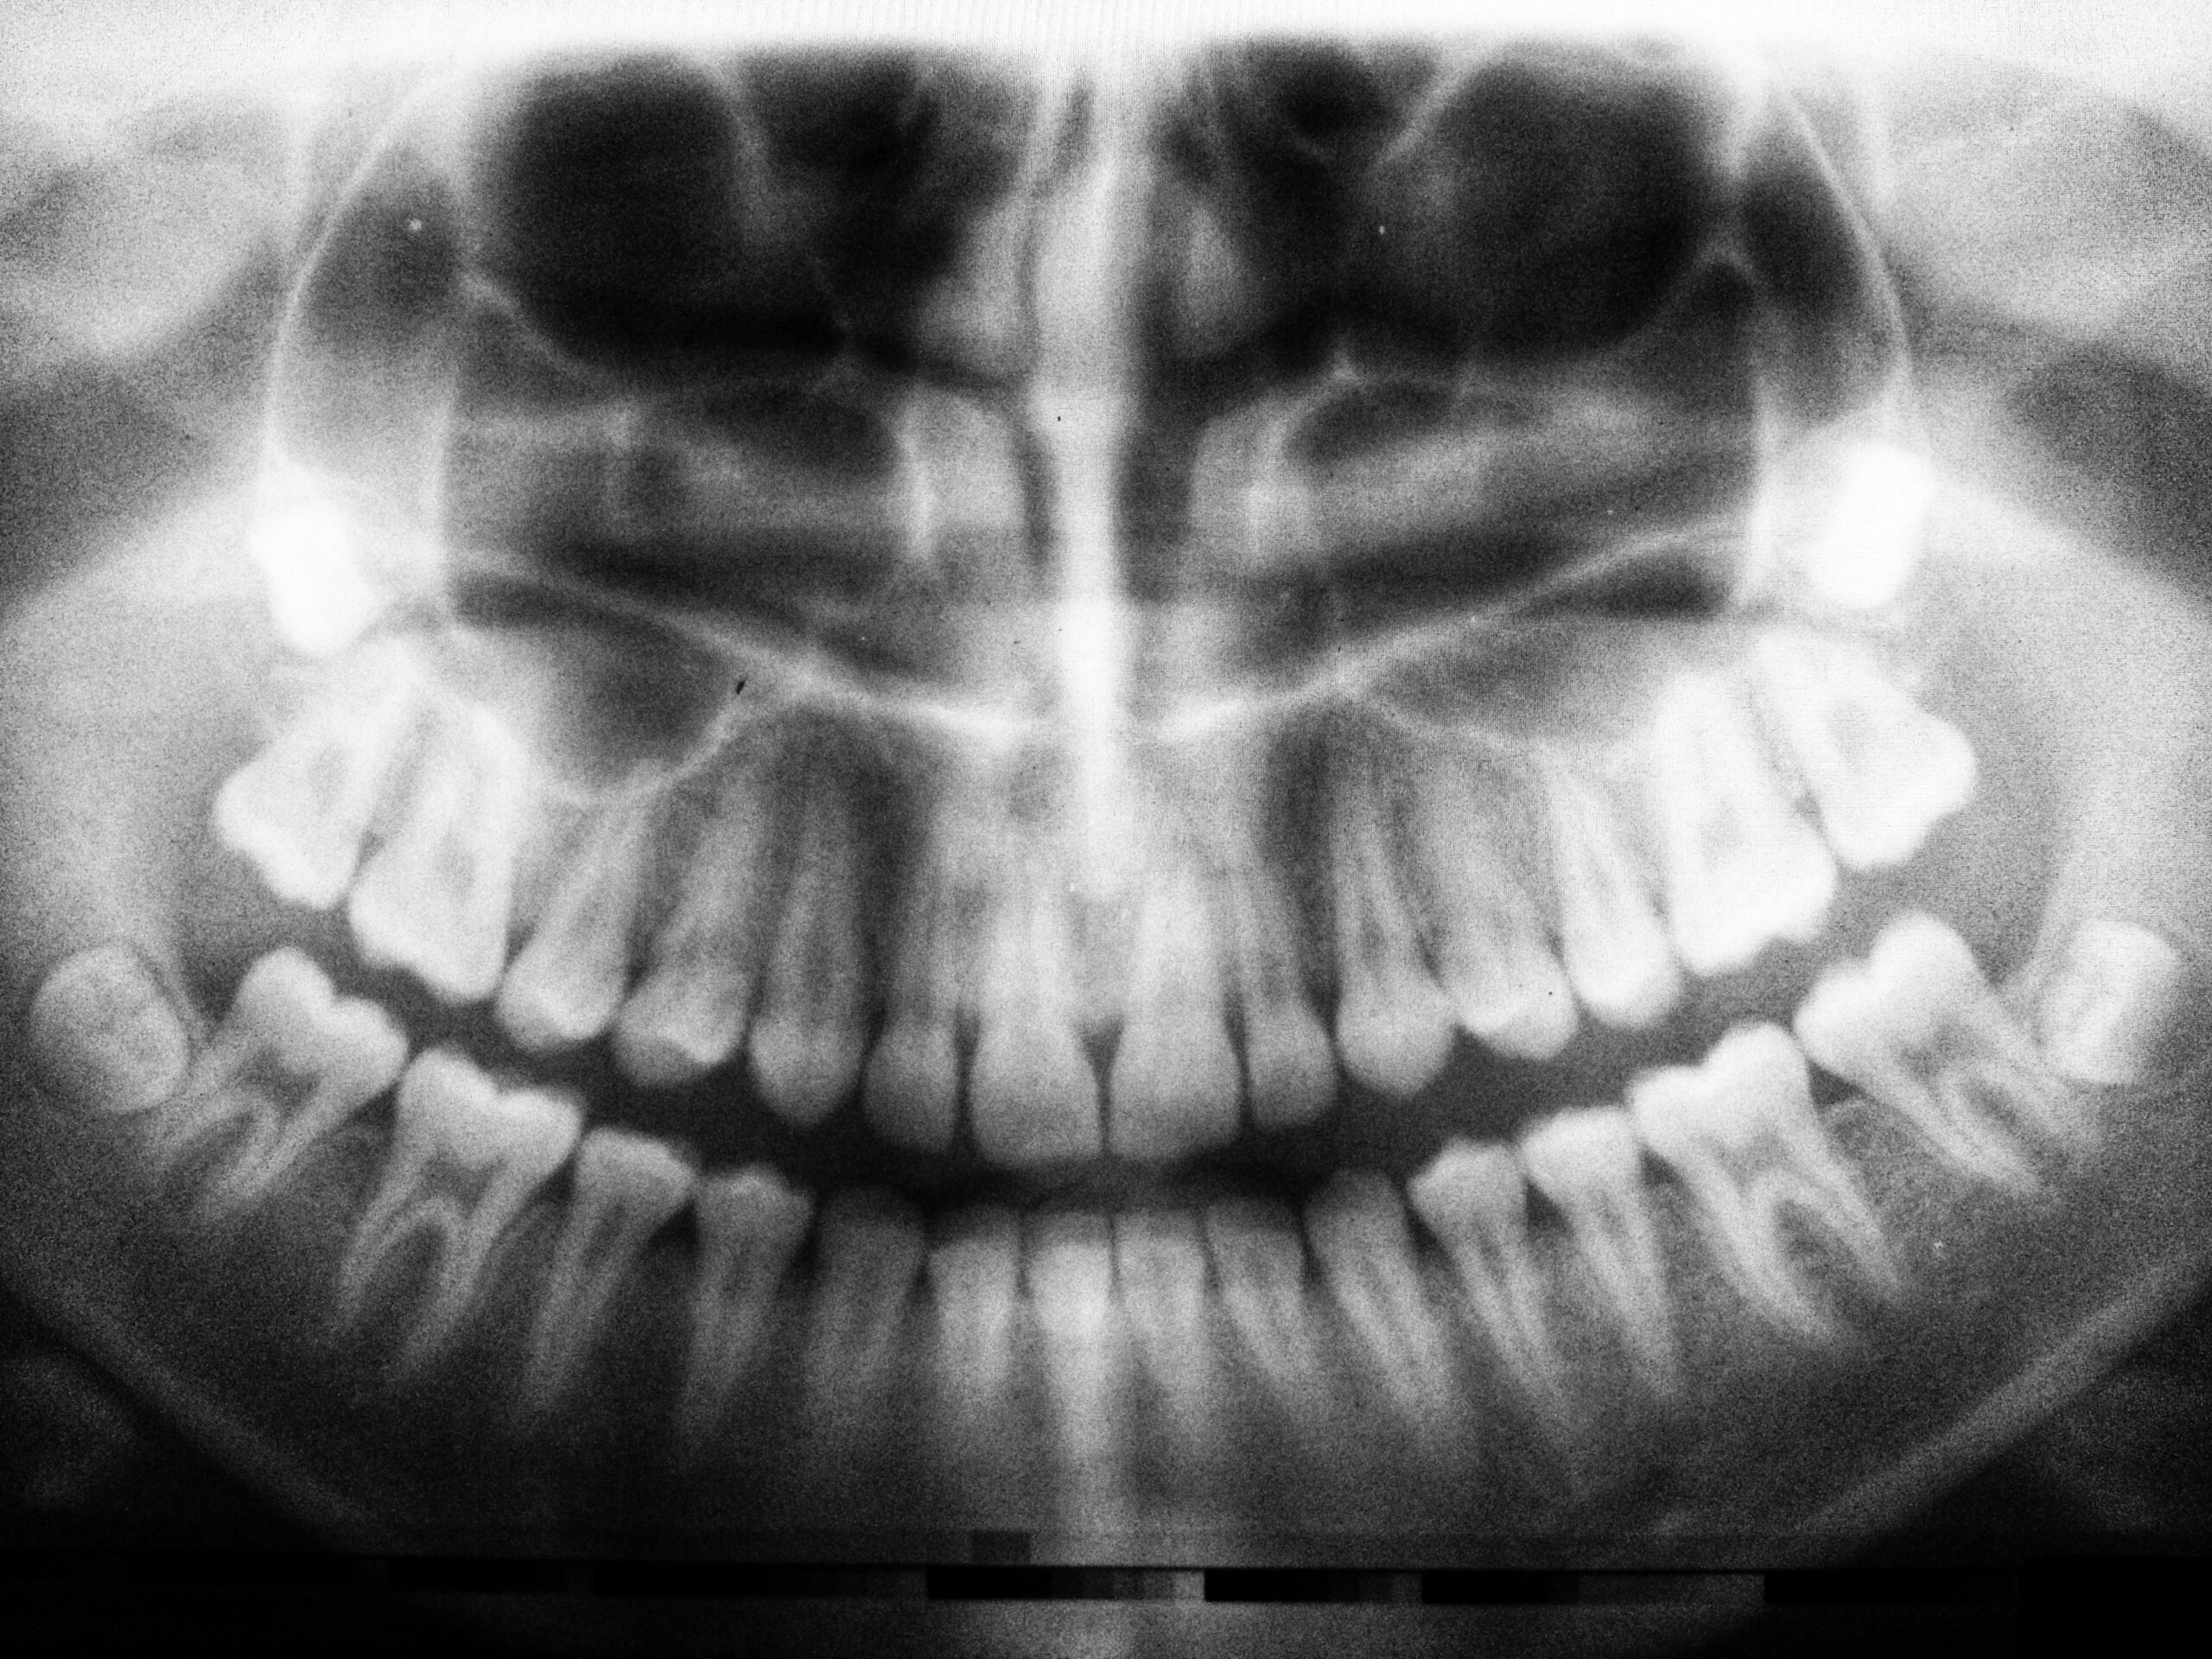

But what about a dental emergency, like a broken tooth? What’s your first step? Don’t be surprised if you don’t know. Most of us aren’t that familiar with the recommendations. But after this post, you’ll be the go-to source if it happens. So What, Exactly, is a Dental Emergency? A dental emergency is any event that warrants […]